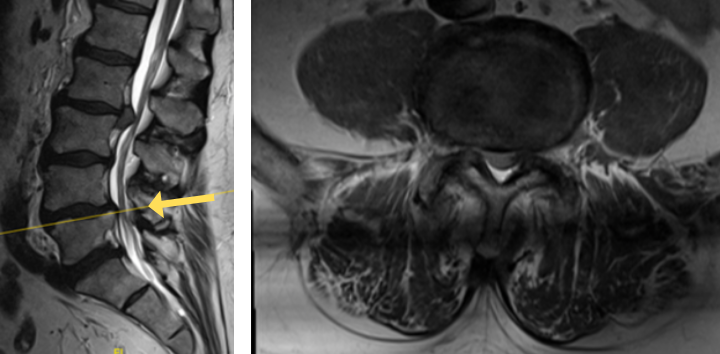

The grade 1 spondylolisthesis at L4/L5 requires both decompression at the L4/L5 level but also fusion because of the instability with motions. Here are three standing x-rays: one in the neutral position, one in flexion, and one in extensions. Notice the movement in the vertebral bodies at L4 and L5. This is abnormal motion and it can contribute to back pain and increase stenosis in certain positions. Thus, it requires decompression and stabilization with fusions.

Image 2. This shows the lumbar spine in motion. Notice the L4 and L5 level changes with flexion and extension. Notice the L2 and L3 levels do not have that type of motion. This is instability.